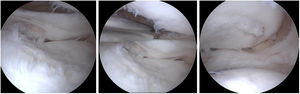

TécnicaBajo anestesia general y uso de torniquete, se realiza abordajes artroscópicos antero lateral y antero medial, se localiza abordaje postero-lateral, tomando como referencia anatómica intraarticular, el tendón poplíteo, y abordaje anterior externo longitudinal de 3cm aproximadamente a nivel de meseta tibial externa, realizando canal óseo de forma trapezoidal, donde se coloca el aloinjerto cadavérico con bloque óseo previamente preparado para encaje a presión y se fija con tornillo canulado de 4.0mm desde superior a inferior en ángulo oblicuo sin afectar a la fisis, corroborando con equipo de fluoroscopía, finalmente se sujeta el menisco mediante fijación periférica hacia la cápsula (figs. 2-6).

Posterior, se talla canal óseo en meseta tibial, paralelo a espinas tibiales, de 8mm cm de profundidad y 1cm de ancho en profundidad y 1cm en parte superficial, logrando un túnel con forma de trapezoide, para no lesionar cartílago de crecimiento, sin perforar cortical posterior y lograr un cerrojo para el momento de colocar el bloque óseo del injerto cadavérico. (Tomado de autores.).

Colocación de puntos de tracción en tercio posterior de injerto meniscal, los mismos que se ingresa por incisión antero lateral, siendo rescatados por abordaje postero lateral, tomando en cuenta que cada punto de tracción se realizó uno por delante y otro posterior a tendón poplíteo. (Tomado de autores).